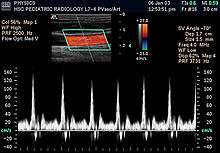

- Doppler mode: This mode makes use of the Doppler effect in measuring and visualizing blood flow

- Color Doppler: Velocity information is presented as a color-coded overlay on top of a B-mode image

- Continuous Doppler: Doppler information is sampled along a line through the body, and all velocities detected at each time point are presented (on a time line)

- Pulsed wave (PW) Doppler: Doppler information is sampled from only a small sample volume (defined in 2D image), and presented on a timeline

- Duplex: a common name for the simultaneous presentation of 2D and (usually) PW Doppler information. (Using modern ultrasound machines, color Doppler is almost always also used; hence the alternative name Triplex.)

Doppler ultrasonography

Sonography can be enhanced with Doppler measurements, which employ the Doppler effect to assess whether structures (usually blood)[16] are moving towards or away from the probe, and its relative velocity. By calculating the frequency shift of a particular sample volume, for example flow in an artery or a jet of blood flow over a heart valve, its speed and direction can be determined and visualised. This is particularly useful in cardiovascular studies (sonography of the vascular system and heart) and essential in many areas such as determining reverse blood flow in the liver vasculature in portal hypertension. The Doppler information is displayed graphically using spectral Doppler, or as an image using color Doppler (directional Doppler) or power Doppler (non directional Doppler). This Doppler shift falls in the audible range and is often presented audibly using stereo speakers: this produces a very distinctive, although synthetic, pulsating sound.

All modern ultrasound scanners use pulsed Doppler to measure velocity. Pulsed wave machines transmit and receive series of pulses. The frequency shift of each pulse is ignored, however the relative phase changes of the pulses are used to obtain the frequency shift (since frequency is the rate of change of phase). The major advantages of pulsed Doppler over continuous wave is that distance information is obtained (the time between the transmitted and received pulses can be converted into a distance with knowledge of the speed of sound) and gain correction is applied. The disadvantage of pulsed Doppler is that the measurements can suffer from aliasing. The terminology "Doppler ultrasound" or "Doppler sonography", has been accepted to apply to both pulsed and continuous Doppler systems despite the different mechanisms by which the velocity is measured.

It should be noted here that there are no standards for the display of color Doppler. Some laboratories show arteries as red and veins as blue, as medical illustrators usually show them, even though some vessels may have portions flowing towards and portions flowing away from the transducer. This results in the illogical appearance of a vessel being partly a vein and partly an artery. Other laboratories use red to indicate flow toward the transducer and blue away from the transducer. Still other laboratories prefer to display the sonographic Doppler color map more in accord with the prior published physics with the red shift representing longer waves of echoes (scattered) from blood flowing away from the transducer; and with blue representing the shorter waves of echoes reflecting from blood flowing toward the transducer. Because of this confusion and lack of standards in the various laboratories, the sonographer must understand the underlying acoustic physics of color Doppler and the physiology of normal and abnormal blood flow in the human body (see Red shift[17][18][19]).

Doppler ultrasonography is used to study blood flow and muscle motion. The different detected speeds are represented in color for ease of interpretation, for example leaky heart valves: the leak shows up as a flash of unique color. Colors may alternatively be used to represent the amplitudes of the received echoes.